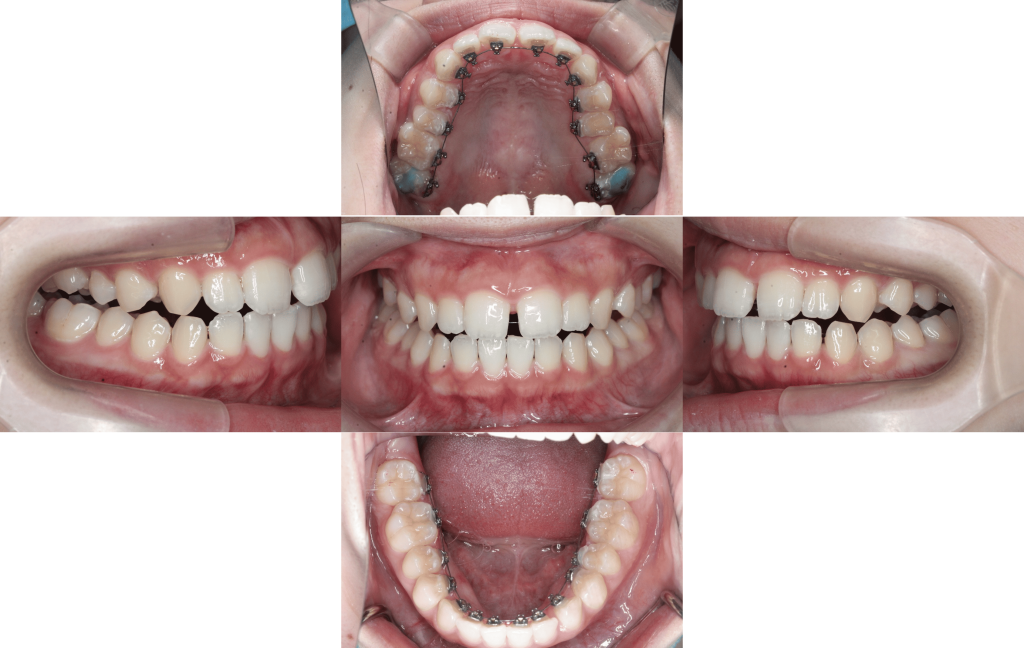

約6か月後